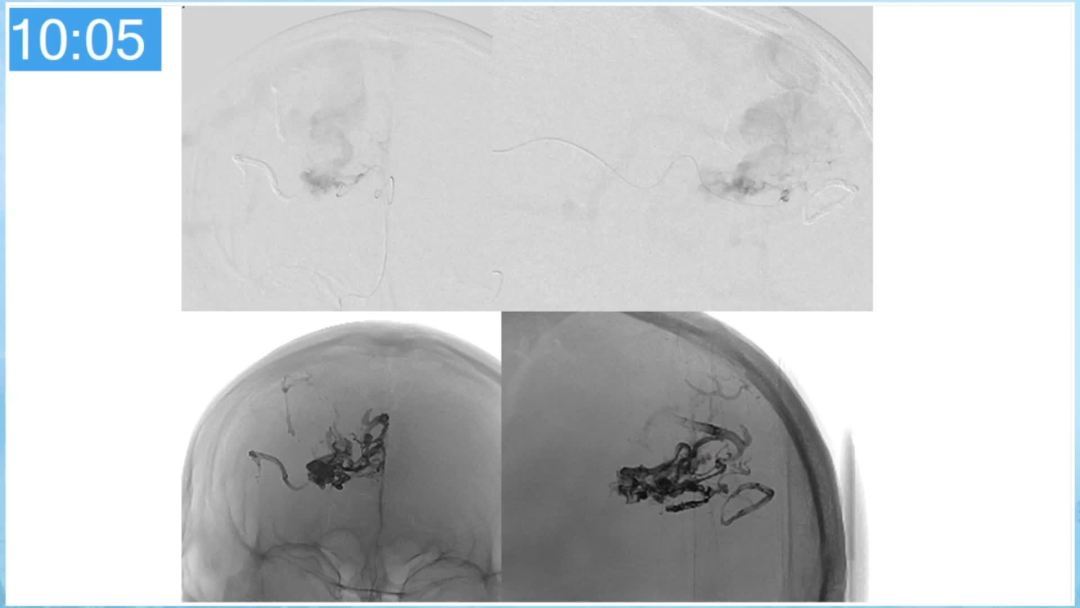

本期为大家特别分享:空军军医大学唐都医院邓剑平教授的精彩会议内容《颅内动静脉畸形的复合手术治疗》,欢迎大家阅读和分享!